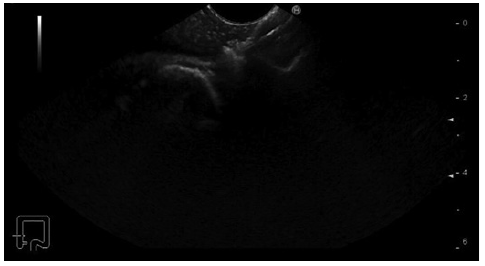

Prior to the puncture, the PFC was carefully evaluated for size and location, ensuring the collection was within 1 cm from the rectosigmoid wall and that no intervening blood vessels would impede the procedure. An electrocautery-enhanced LAMS delivery system (Hot-Axios®; Boston Scientific, Marlborough, MA, USA) with a stent diameter of 15 or 20 mm was used based on the endoscopist’s discretion and availability at the time of the procedure. The ERBE VIO 200D electrosurgical unit, using AUTOCUT mode, effect 5, power 100 W, was employed for the transrectal puncture with the Hot-Axios® system. The direct puncture technique was performed under EUS guidance alone (without fluoroscopic assistance). The distal phalanx deployment was executed under ultrasound visualization, while the proximal phalanx release was conducted with endoscopic or/and ultrasound view (Fig. 1, 2).